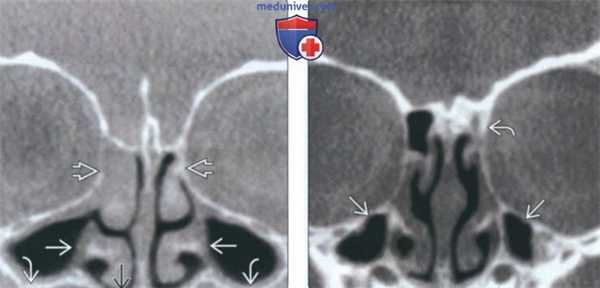

(Слева) На сагиттальной КЛКТ (реконструкций) визуализируется большое куполообразное объемное образование без кортикальной пластинки с плотностью мягких тканей (гиперденсное относительно воздуха), сопоставимое с муцинозной ретенционной псевдокистой верхнечелюстной пазухи. Край пазухи возле кисты интактен.

(Справа) На аксиальной КЛКТ (реконструкция) визуализируется муцинозная ретенционная псевдокиста, занимающая всю камеру правой верхнечелюстной пазухи на этом уровне. Важно не спутать перегородку в пазухе с кортикальной пластинкой на периферии образования. Обратите внимание на утолщение слизистой оболочки камер левой верхнечелюстной пазухи.

(Слева) На периапикальной рентгенограмме задних отделов верхней челюсти справа, не содержащей зубов, на фоне воздуха визуализируется куполообразное затемнение в верхнечелюстной пазухе. Край пазухи возле затемнения интактен. Обратите внимание на наложение скулового отростка.

(Справа) На корональной КЛКТ (реконструкция) визуализируется куполообразная ретенционная псевдокиста в правой верхнечелюстной пазухе. Кортикальная пластинка на периферии псведокисты отсутствует, края пазухи интактны.

(Слева) На сагиттальной КЛКТ (реконструкция) у пациента с гипоплазией верхнечелюстных пазух определяется также аплазия сфеноидальных и лобных пазух.

(Справа) На корональной КЛКТ (реконструкция) у этого же пациента не видны лобные пазухи с обеих сторон, что позволя ет сделать вывод об аплазии. Гипоплазия/аплазия лобных пазух наблюдается чаще по сравнению с другими околоносовыми пазухами.

(Слева) На корональной КЛКТ в нижней части изображения визуализируется дно гипопластической ВП, находящееся выше дна носовых ямок. Утолщена слизистая оболочка обеих верхнечелюстных пазух. Решетчатые пазухи отсутствуют.

(Справа) На корональной КЛКТ определяется гипоплазия обеих ВП и аплазия левой решетчатой пазухи.

(Слева) На аксиальной КЛКТ (реконструкция) у этого же пациента определяется гипоплазия верхнечелюстных пазух. Обе сфеноидальные пазухи ИЯ выглядят рудиментарными, что сопоставимо с их выраженной гипоплазией.

(Справа) На корональной КЛКТ (реконструкция) у этого же пациента определяется выраженное недоразвитие обеих сфеноидальных пазух. Гипоплазия/аплазия сфеноидальных пазух встречается реже, чем решетчатых или лобных.